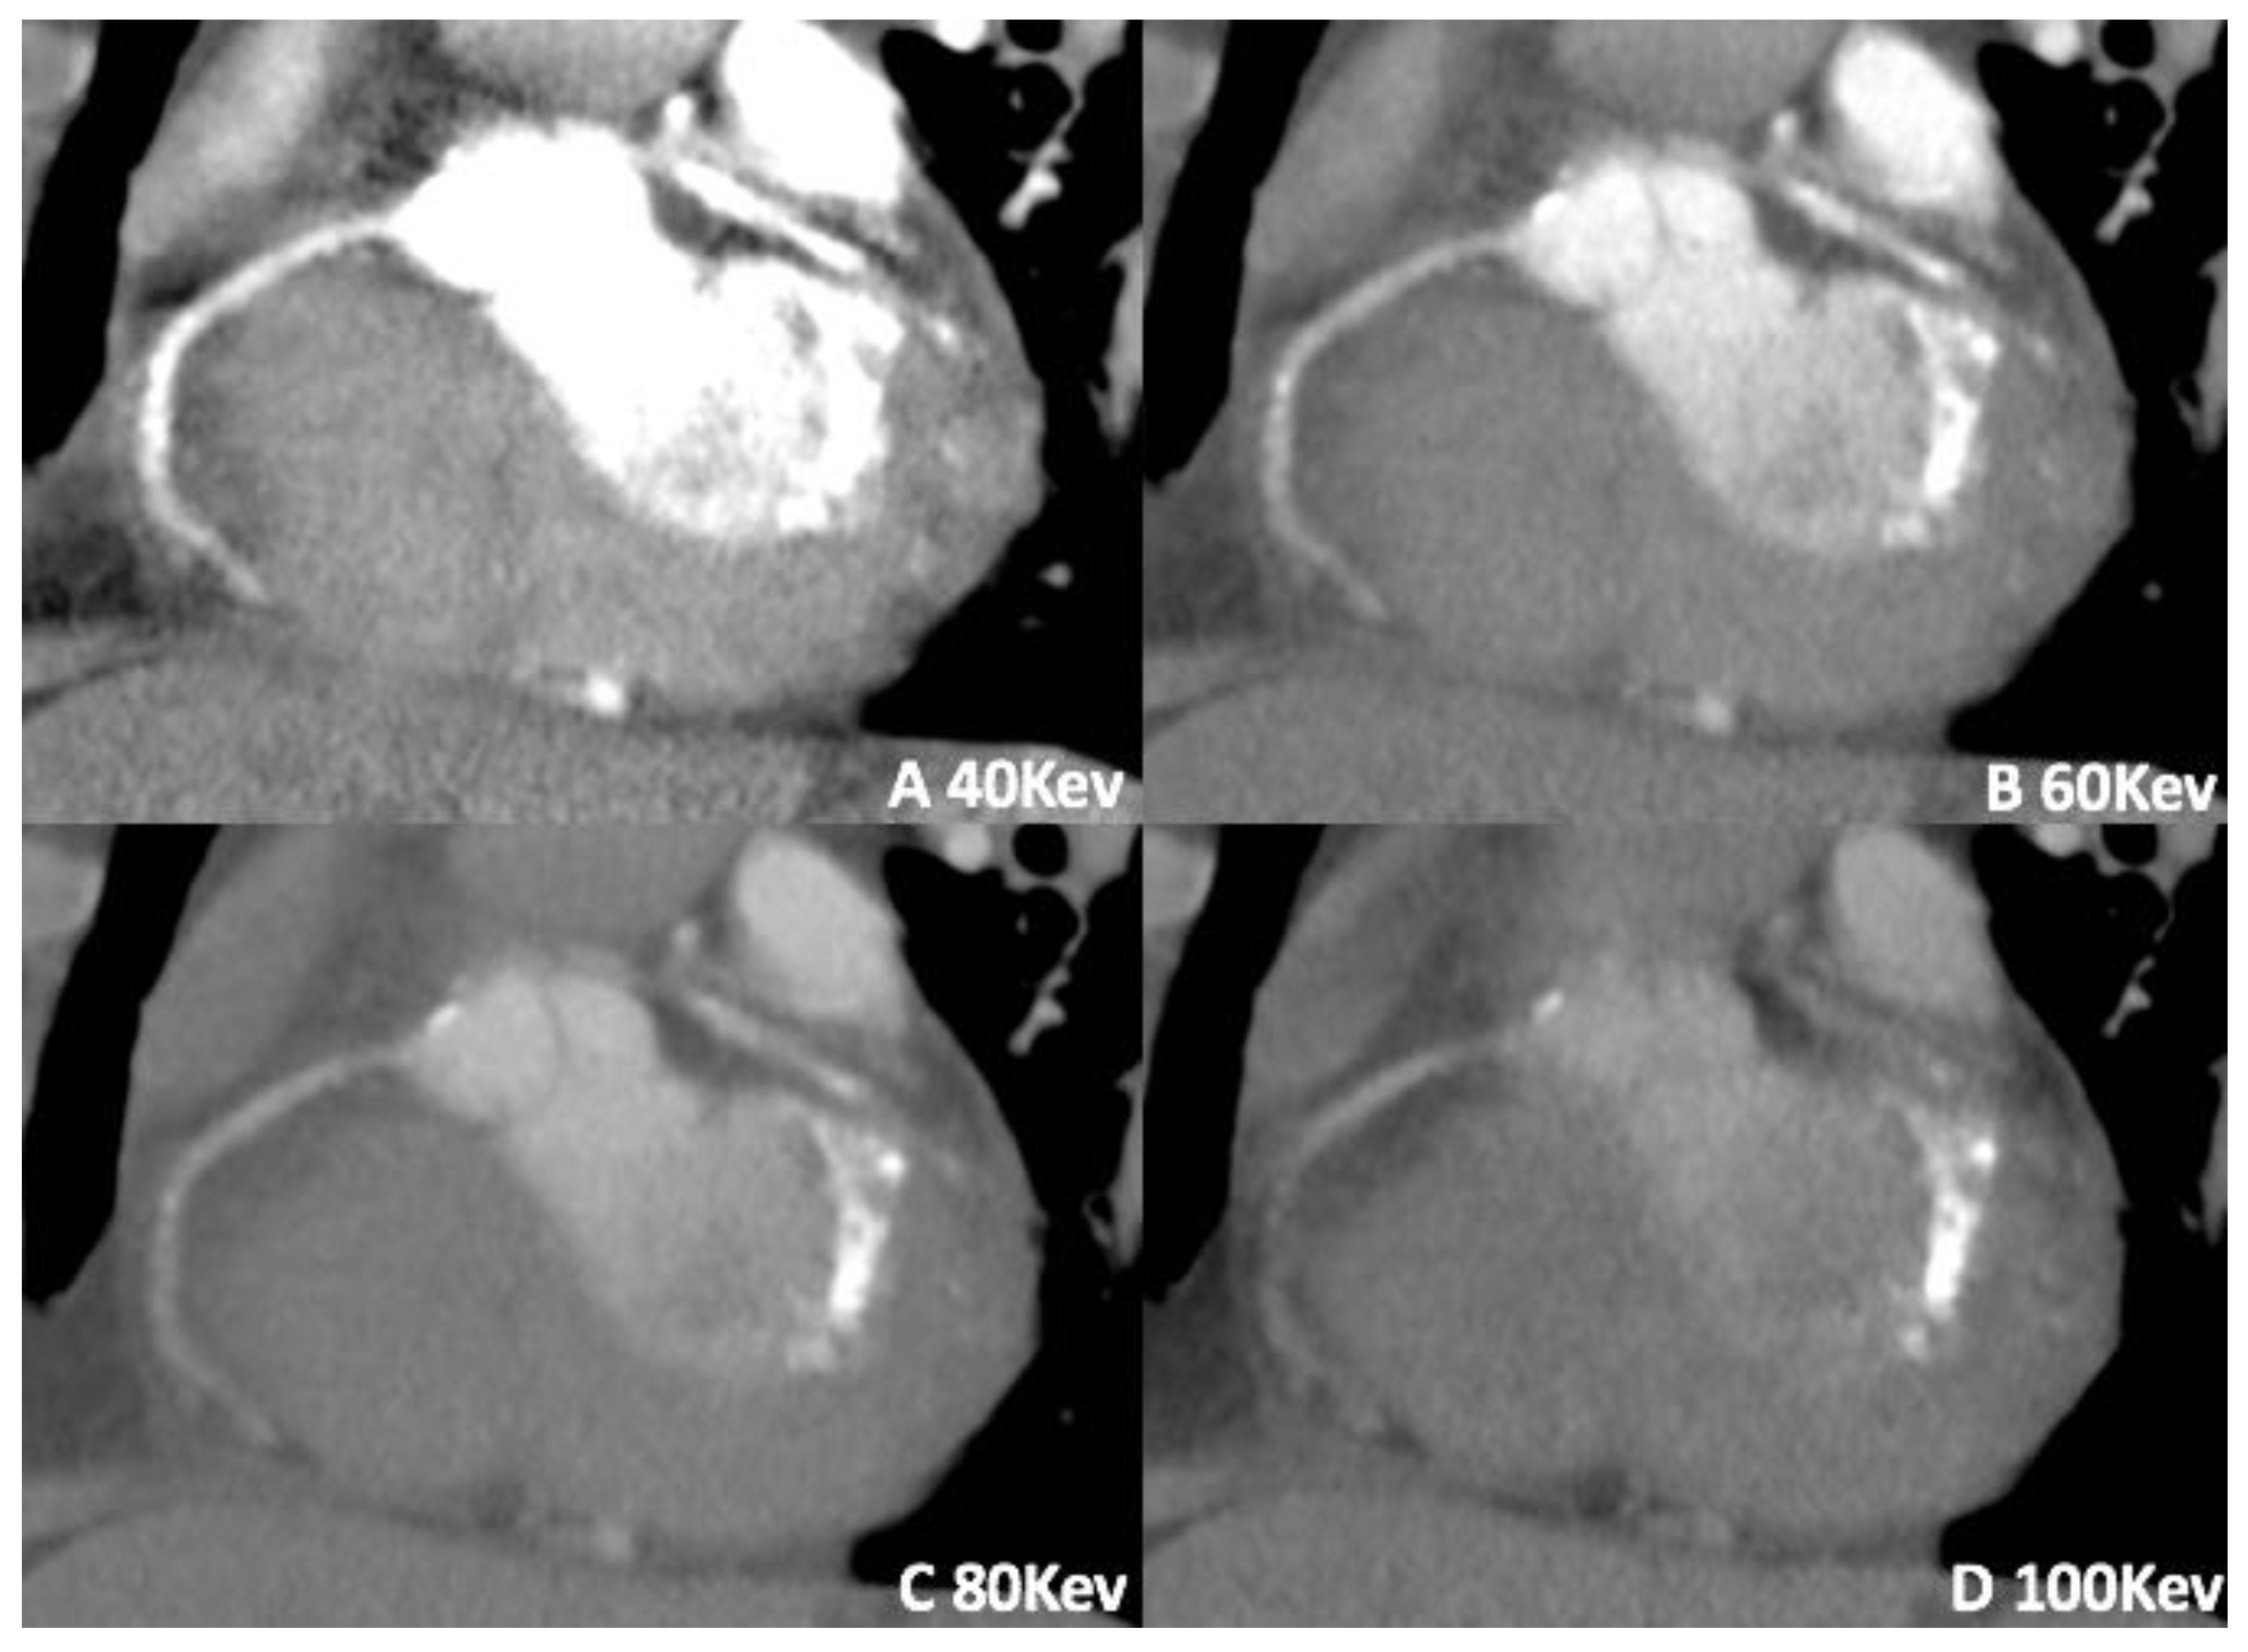

3.1. Virtual Monoenergetic Imaging (VMI)

- Chang, S.; Han, K.; Youn, J.-C.; Im, D.J.; Kim, J.Y.; Suh, Y.J.; Hong, Y.J.; Hur, J.; Kim, Y.J.; Choi, B.W.; et al. Utility of Dual-Energy CT-based Monochromatic Imaging in the Assessment of Myocardial Delayed Enhancement in Patients with Cardiomyopathy. Radiology 2018, 287, 442–451. [Google Scholar] [CrossRef] [PubMed]

- Wichmann, J.L.; Arbaciauskaite, R.; Kerl, J.M.; Frellesen, C.; Bodelle, B.; Lehnert, T.; Monsefi, N.; Vogl, T.J.; Bauer, R.W. Evaluation of monoenergetic late iodine enhancement dual-energy computed tomography for imaging of chronic myocardial infarction. Eur. Radiol. 2014, 24, 1211–1218. [Google Scholar] [CrossRef] [PubMed]

- Lenga, L.; Albrecht, M.H.; Othman, A.E.; Martin, S.S.; Leithner, D.; D’Angelo, T.; Arendt, C.; Scholtz, J.-E.; De Cecco, C.N.; Schoepf, U.J.; et al. Monoenergetic Dual-energy Computed Tomographic Imaging: Cardiothoracic Applications. J. Thorac. Imaging 2017, 32, 151–158. [Google Scholar] [CrossRef]